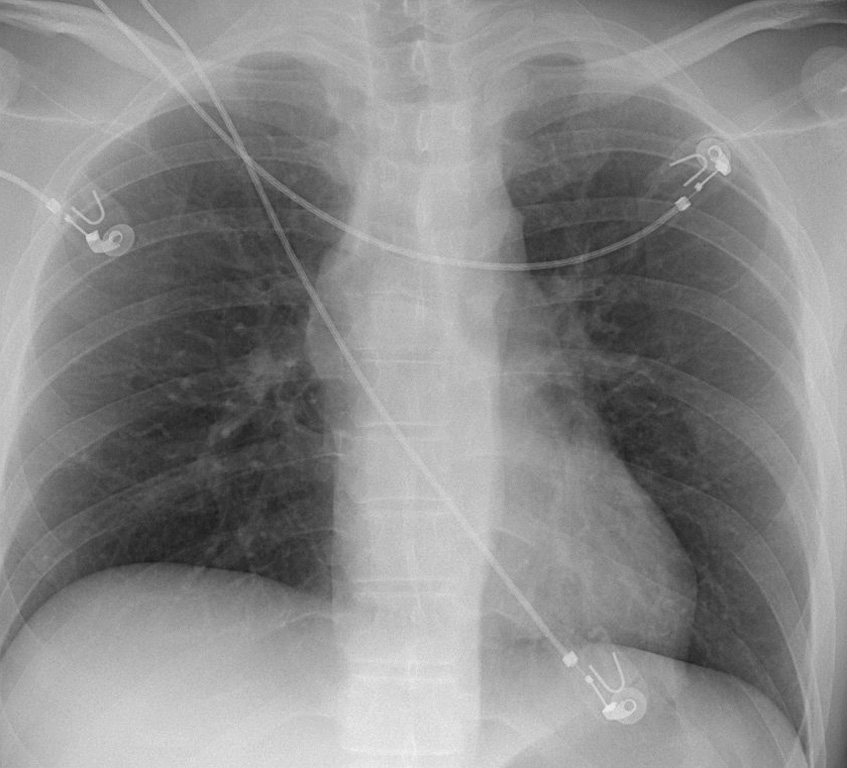

Gallery Blunt Chest Trauma Spine trauma Case 3a

Case 3a